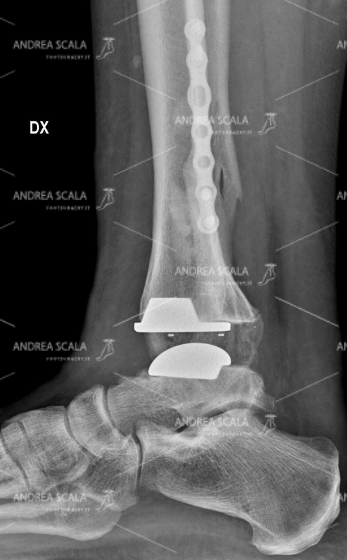

La RXgrafia anteriore della caviglia mostra la protesi della caviglia. 5 anni dopo la frattura, all’età di 39 anni, la paziente ha rifiutato l’artrodesi, cioè il blocco della caviglia e si è sottoposta all’intervento di protesi di caviglia. Si vede molto bene che la placca e le viti sul perone sono rimaste al loro posto indisturbate. Il perone non è stato toccato perché è un elemento anatomico che garantisce la stabilità della caviglia. Le componenti appaiono ben allineate all’asse della gamba.

La RXgrafia laterale della caviglia mostra la protesi della caviglia. Per quale motivo si sarebbe dovuto rompere nuovamente il perone? Perché avrebbe dovuto sacrificare una parte che era guarita? Perché avrebbe dovuto rompere di nuovo una parte che aveva impiegato tanto tempo a consolidare e a guarire? Per fare un favore a chi? Si nota che le componenti della protesi sono parallele al piano d’appoggio al suolo.